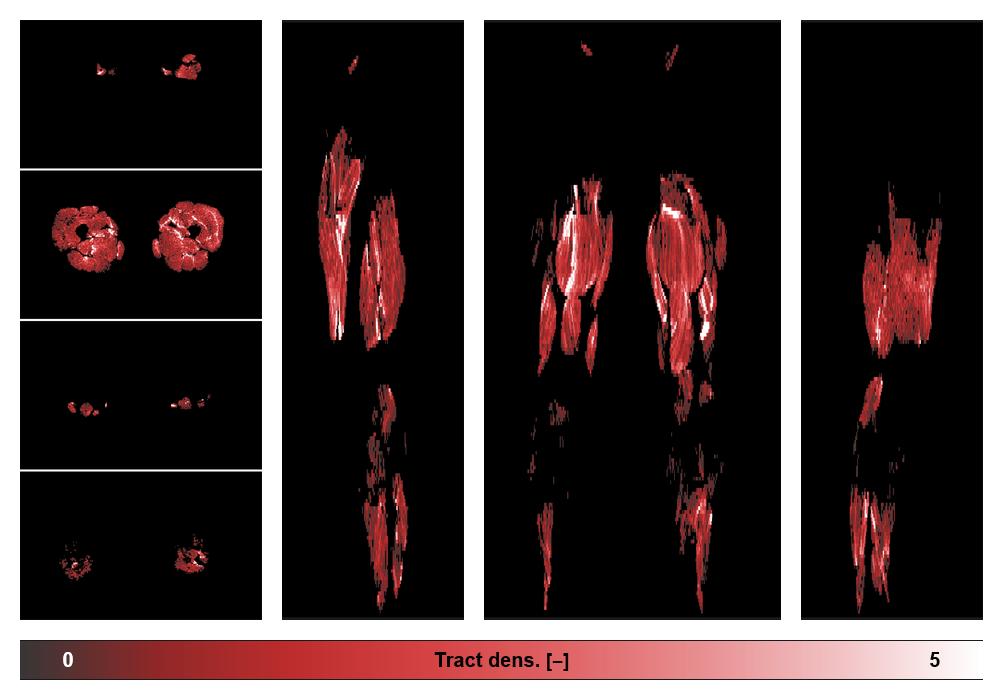

• Muscle fiber density map

Muscle fiber tract density map based on whole leg DTI based fiber tractography.